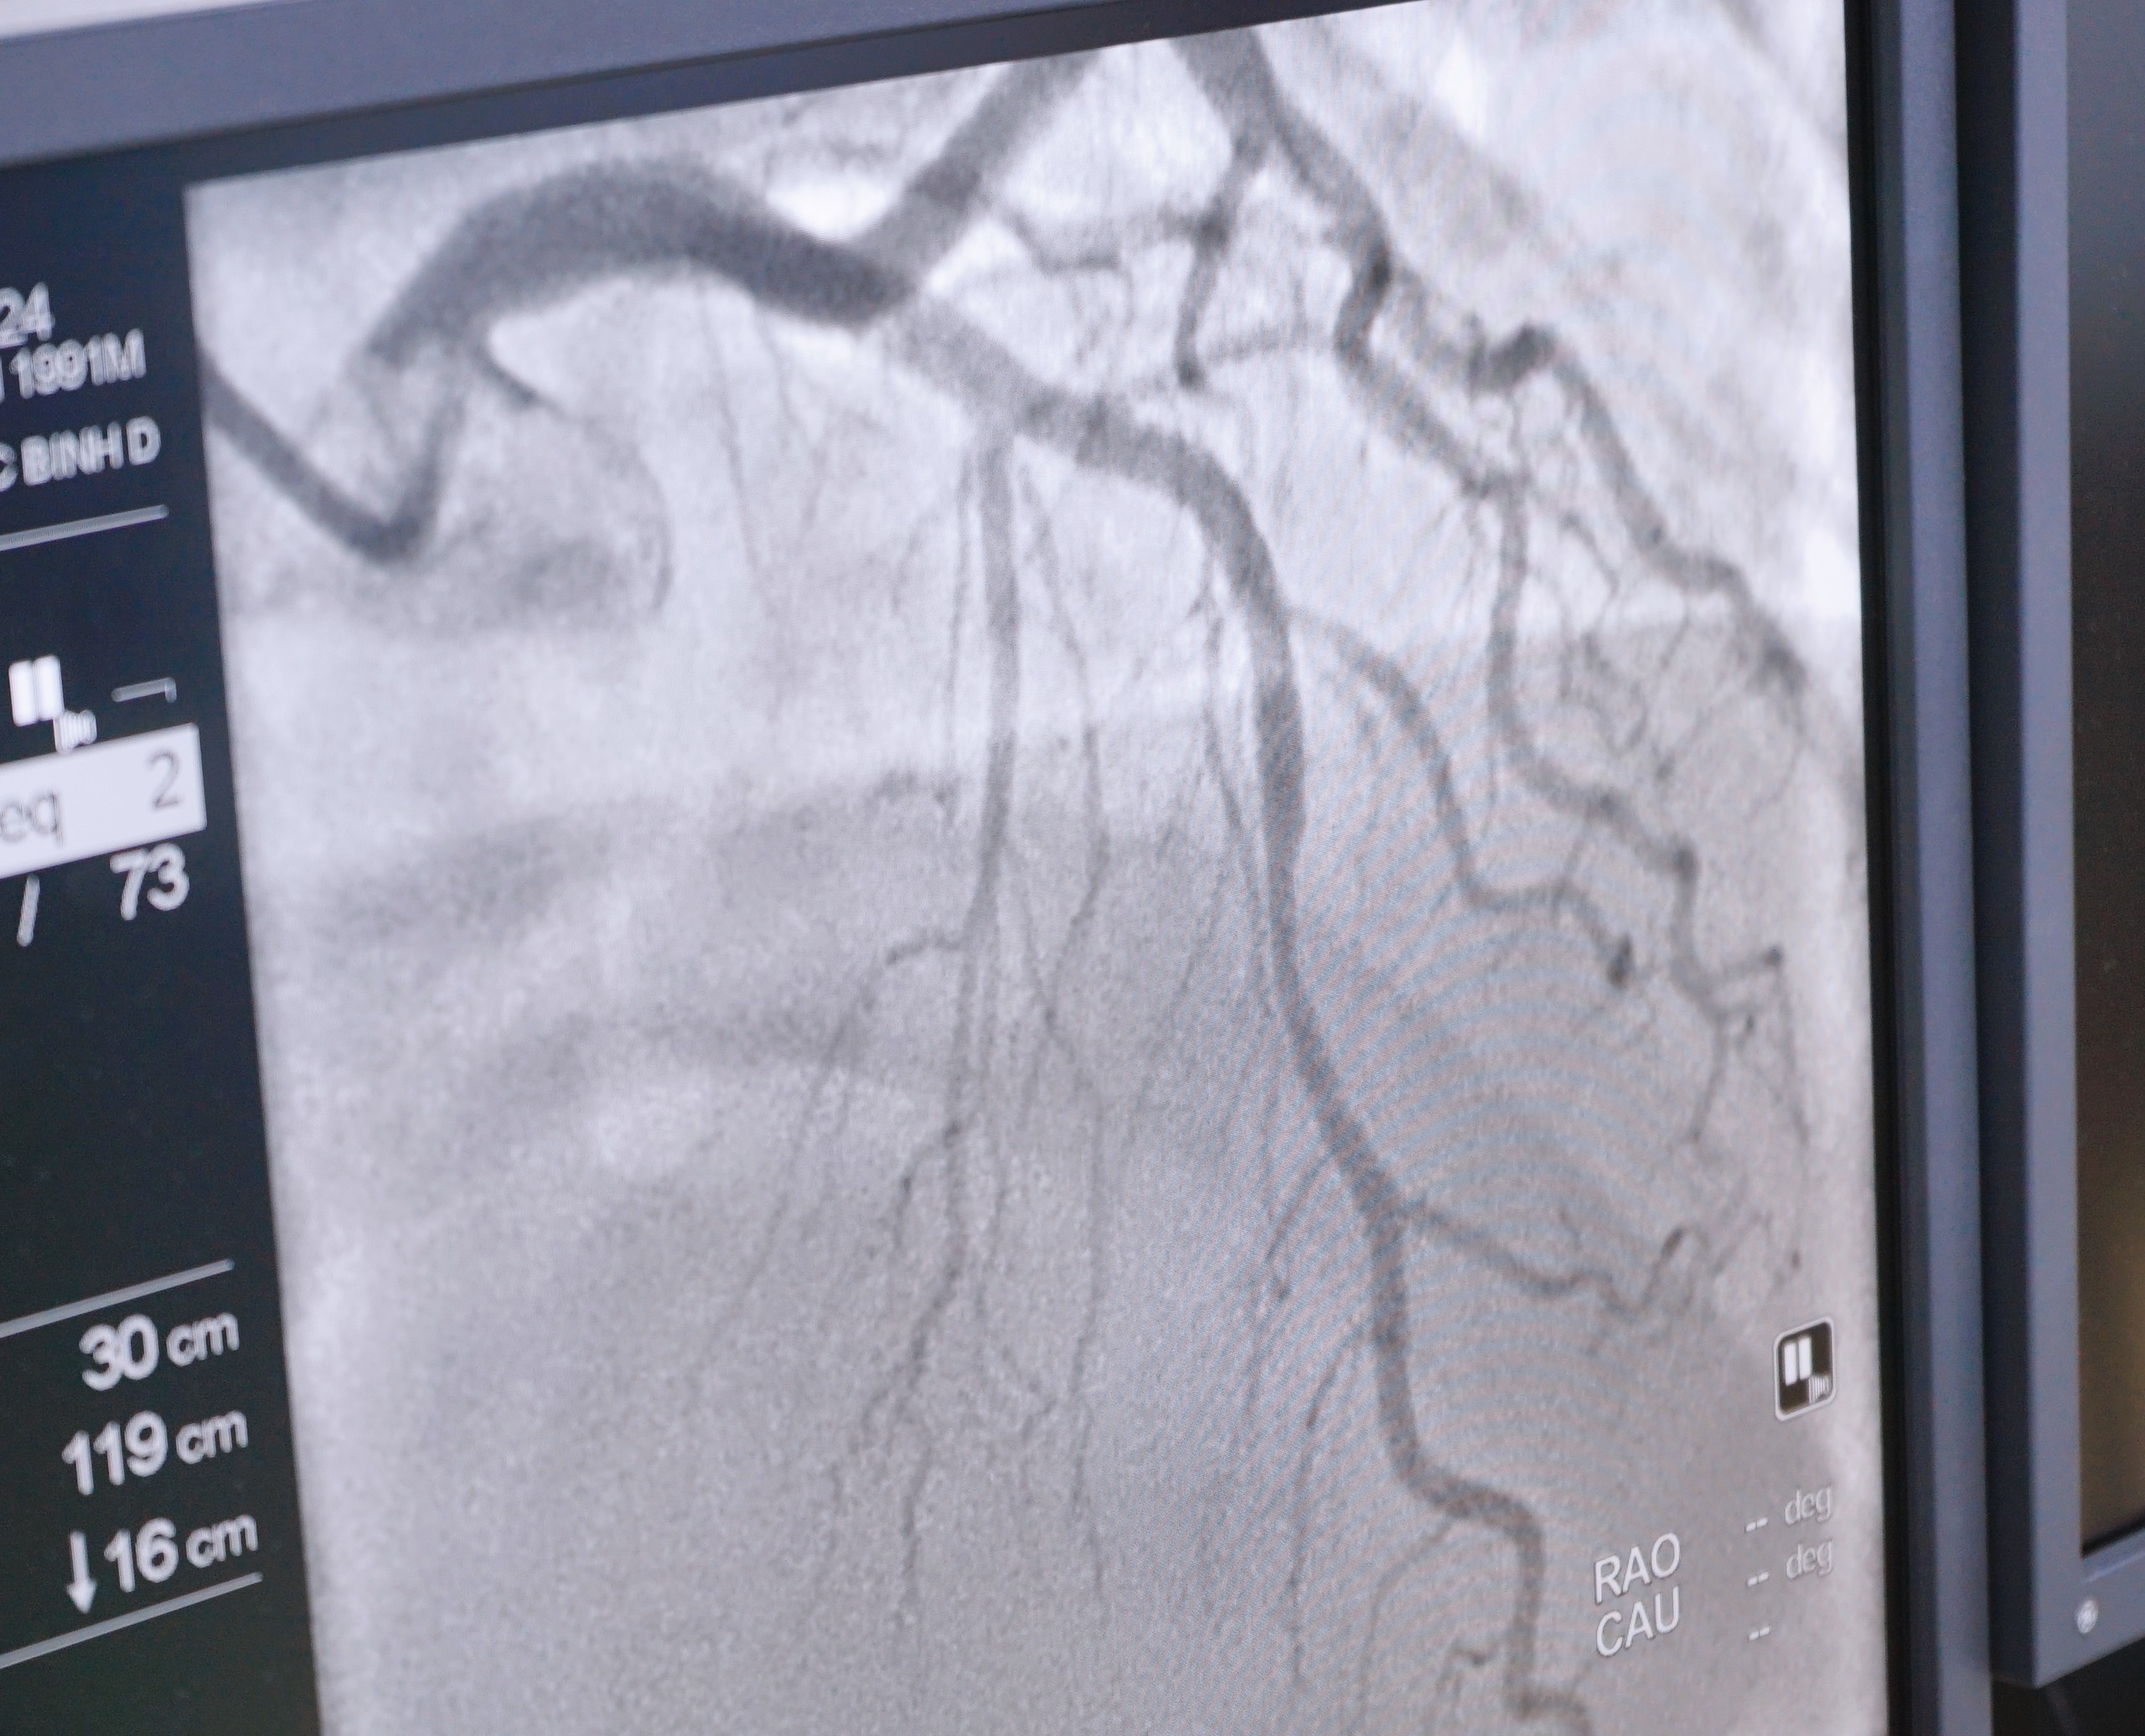

Chụp mạch máu số hóa xóa nền (DSA)

Bệnh nhân: B.V.M sinh năm 1956 - Bắc Tân Uyên - Bình Dương. Khi biết bệnh viện đa khoa Medic Bình Dương đưa vào hoạt động kỹ thuật chụp mạch vành đã đến đăng ký thực hiện ngay để tầm soát sức khỏe của "Trái Tim".

Sau khi chụp mạch vành, bệnh nhân cảm thấy rất vui vì đã tìm ra nguyên nhân do hẹp 2/3 nhánh Tim và có phương án xử lý kịp thời, nếu để lâu sẽ có nguy cơ dẫn đến suy tim và đột tử.